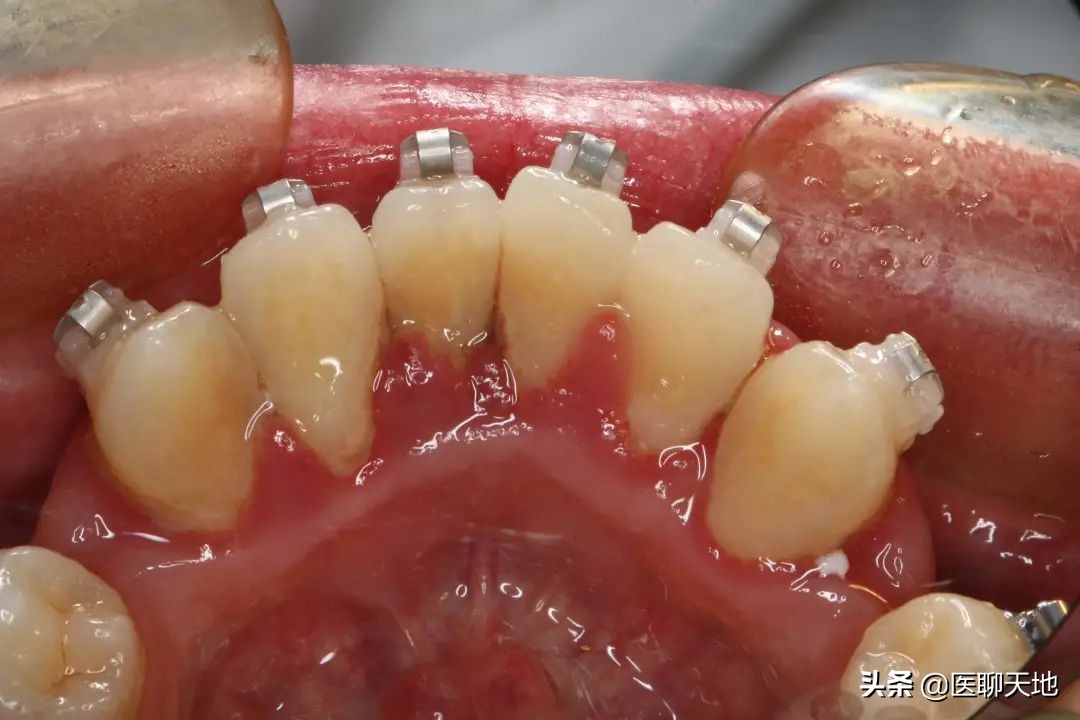

正畸治疗前,有牙龈炎及轻度牙周炎的患者,可以在正畸前进行口腔洁治及定期的口腔维护,待牙周炎症稳定后可开始正畸治疗,治疗过程中须定期进行牙周维护以保证牙周状态的稳定。

对于中度牙周炎的患者,不建议贸然进行正畸治疗,在正畸医生及牙周医生共同评估正畸治疗风险后,经过系统的牙周治疗后,牙周状态稳定的情况下,才能尝试进行正畸治疗。